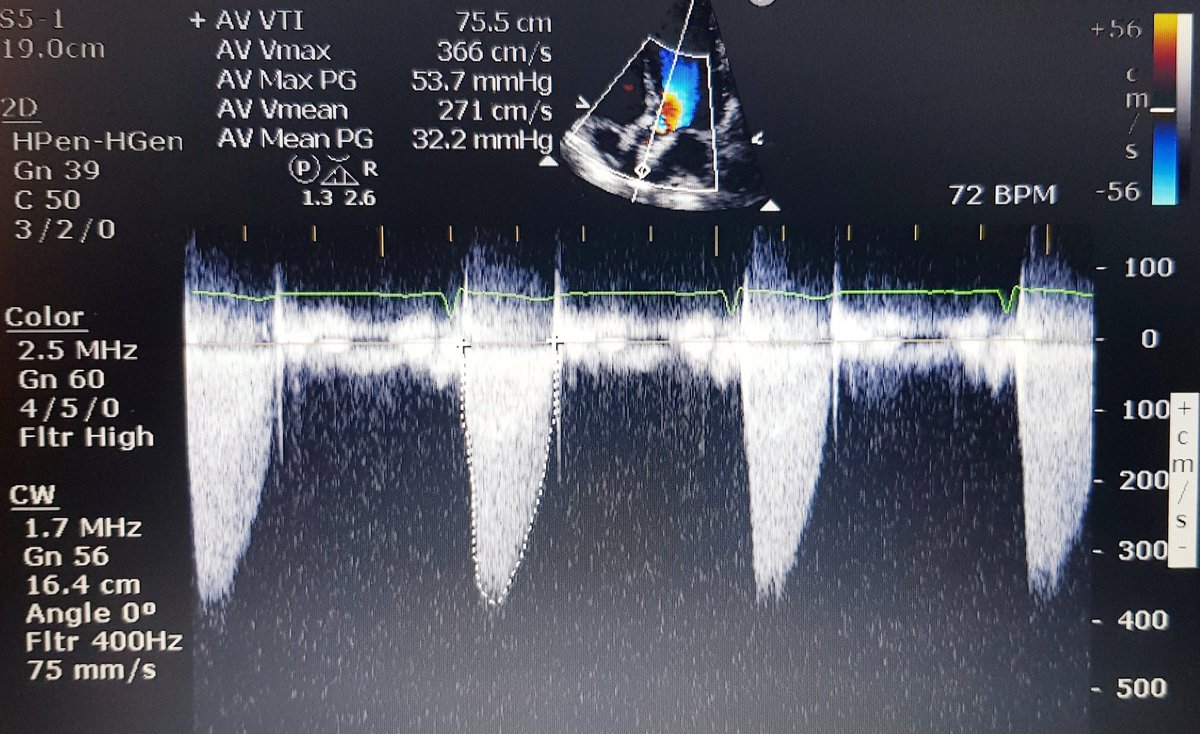

Here is pre-discharge TTE:

6 months later patient feels fine, active and asymptomatic. But has AV Vmax 3.6-3.7m/s...in early 60s. How long will this last? Only time will tell!